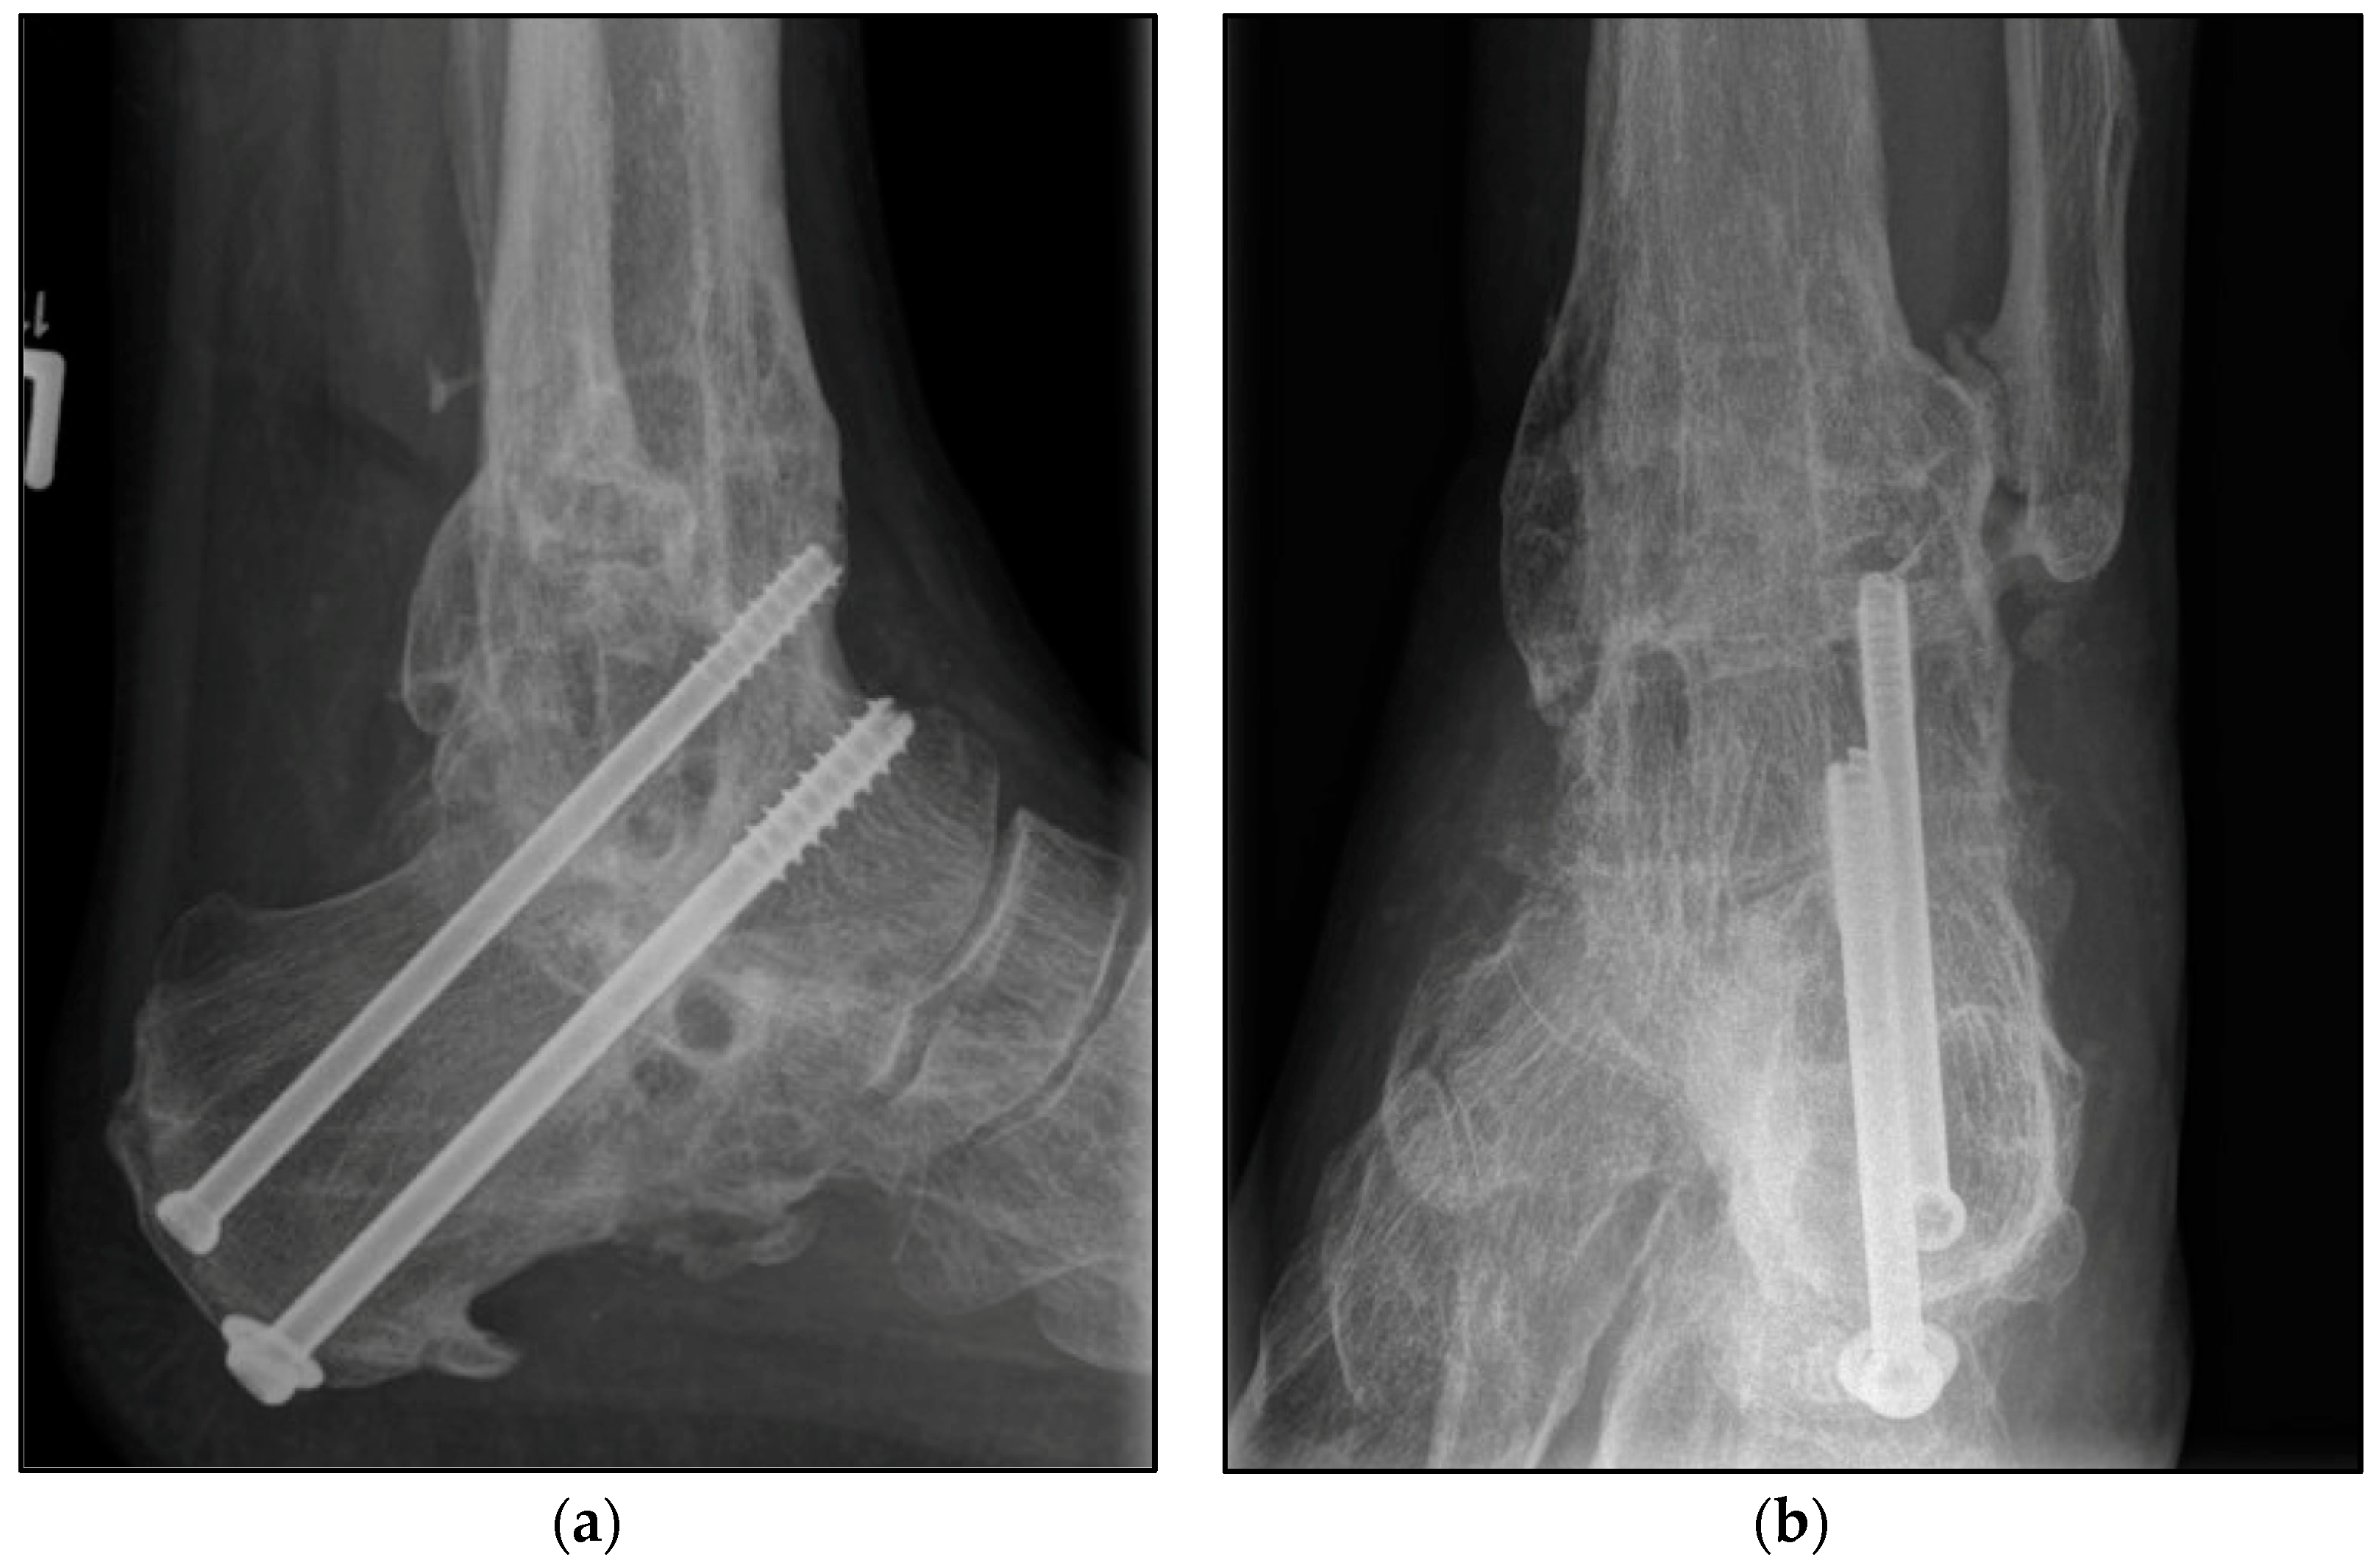

2.3. Surgical Procedure